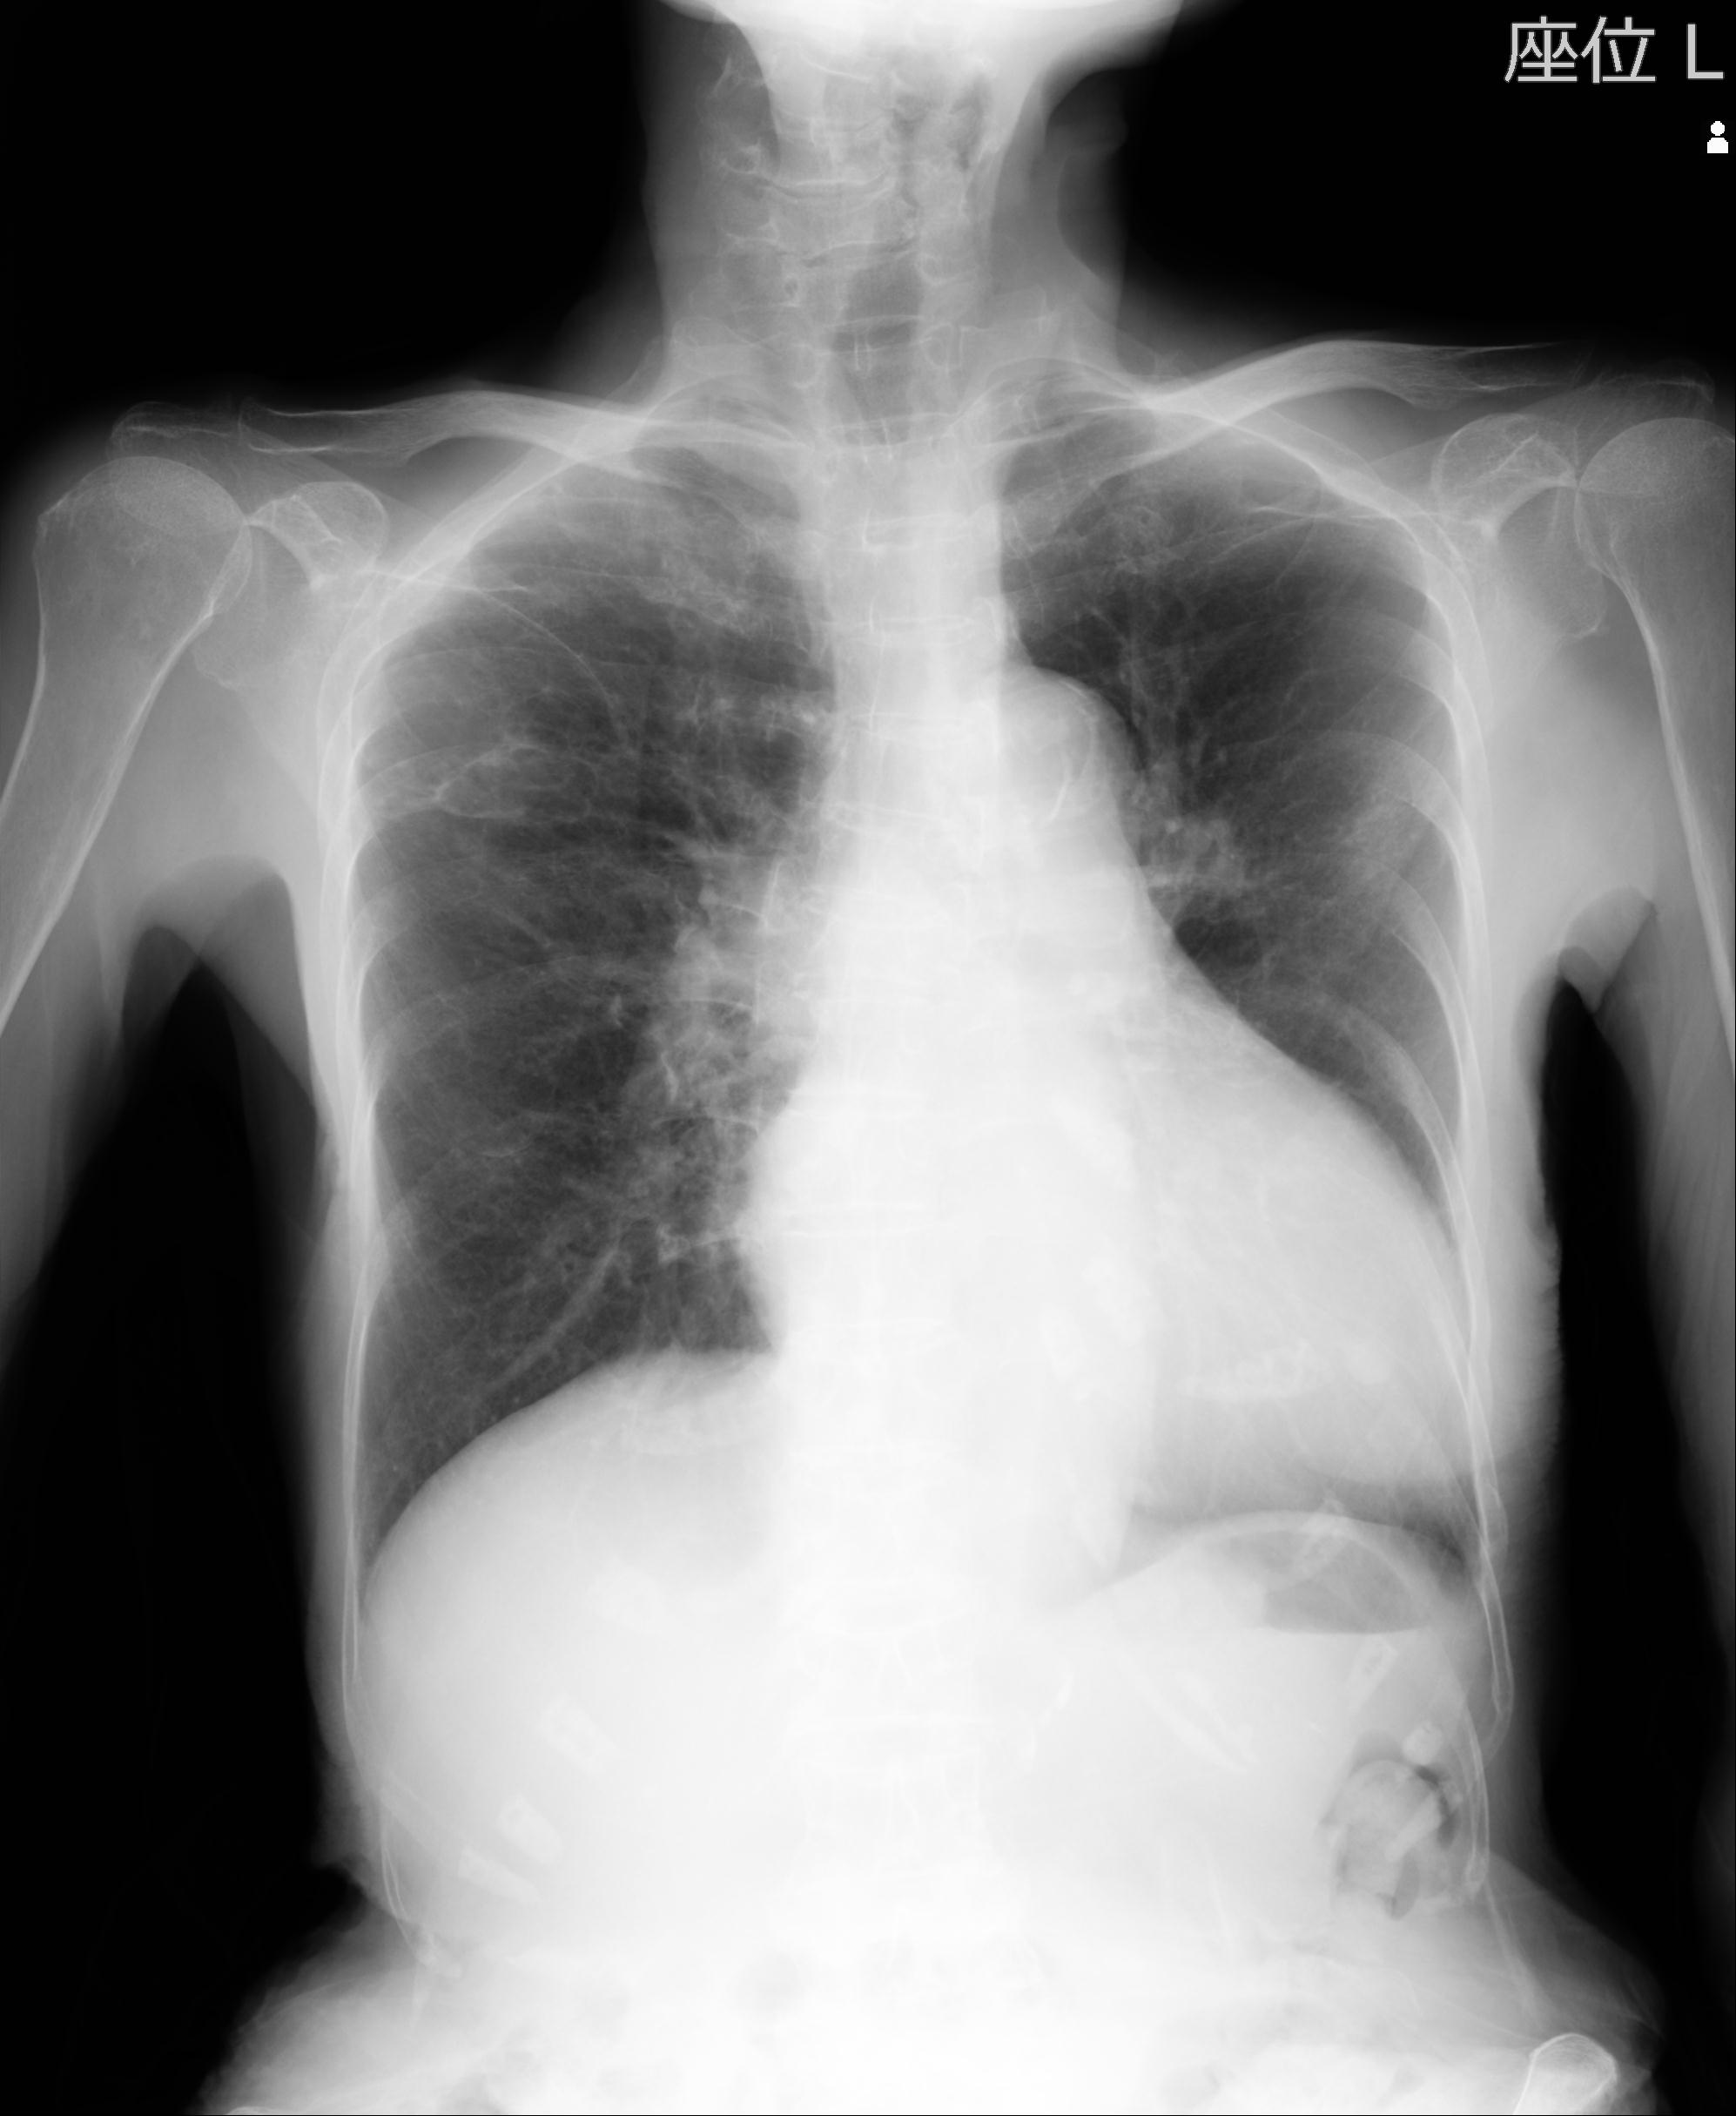

110214 12/20 肩 2R 12/21 肩 4R 72歳女性 左上腕外科頚プレート